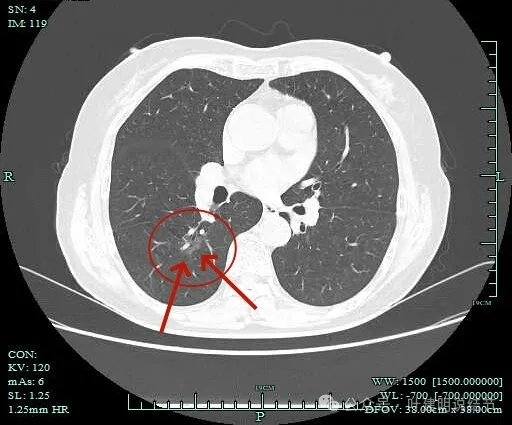

病灶出现,淡磨玻璃密度,但轮廓较清,且表面不平。

病灶内部有走行的支气管,但显得有些僵硬;病灶表面有浅分叶。

灶内血管走行,轮廓与边界清楚。

边缘有毛刺征!

沿支气管走行方向延伸,磨玻璃密度,且支气管内壁显得毛糙。

毛刺明显,轮廓清楚,灶内支气管扩张通气。

毛刺明显,灶内有实性成分出现。

毛刺征明显!!灶内密度杂乱。

实性成分较多,边缘毛刺。

毛刺征明显,而且是短毛刺且锐利。

毛刺。

边缘区也不光滑,显毛糙。

靶重建显示混合密度,边缘毛糙,内部杂乱,灶内支气管通气且僵硬。

病灶影响到斜裂肺门部,边缘毛刺明显。灶内支气管僵硬。

密度杂乱,毛刺明显,支气管僵硬。

杂乱密度,整体轮廓较清,边缘毛糙。

斜裂根部有增厚并与病灶连着。考虑是肿瘤已经侵及叶间裂。

病灶边缘毛刺明显。

肺磨玻璃结节我们常说瘤肺边界清楚加上随访持续存在,基本上是肺癌性质的。但像今天这种混合磨玻璃密度的病灶,你看它瘤肺边界却是不清楚的,只是整体轮廓相对较清。但它的瘤肺边界是布满细毛刺的,而且是短毛刺且锐利,在影像上就像刺入周围正常肺组织中。这种影像表现的我将它称为“浸润性生长的影像表现”,说明病灶是浸润性病灶,而非原位癌或良性。这样的病灶不宜过度随访,需要及时干预更为稳当。